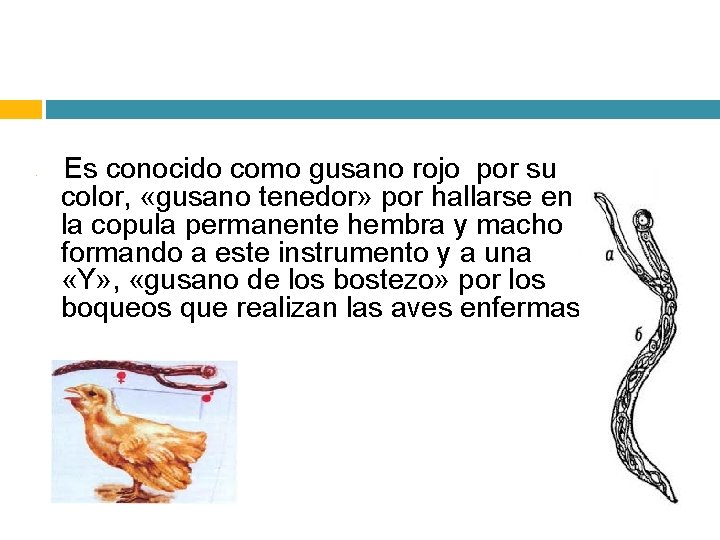

• Es conocido como gusano rojo por su color, «gusano tenedor» por hallarse en la copula permanente hembra y macho formando a este instrumento y a una «Y» , «gusano de los bostezo» por los boqueos que realizan las aves enfermas.